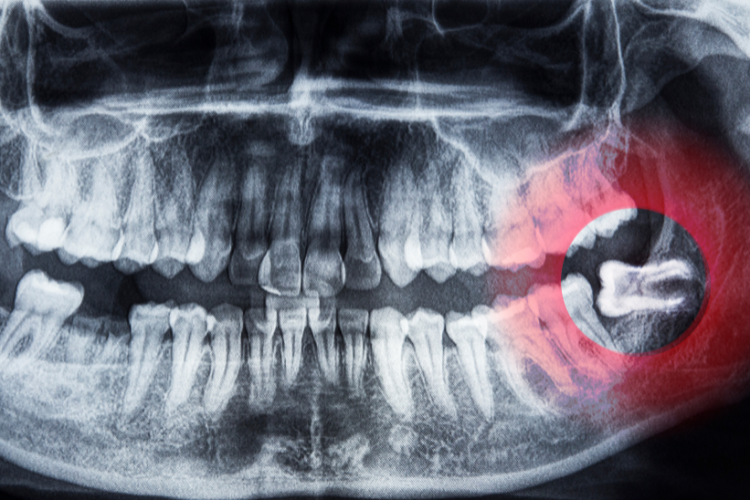

- Impacted Teeth: Teeth that don’t fully erupt can cause pain, infections, or cysts.

Regular dental visits and X-rays help determine if your wisdom teeth will cause future issues. Acting early can prevent unnecessary pain or complications.